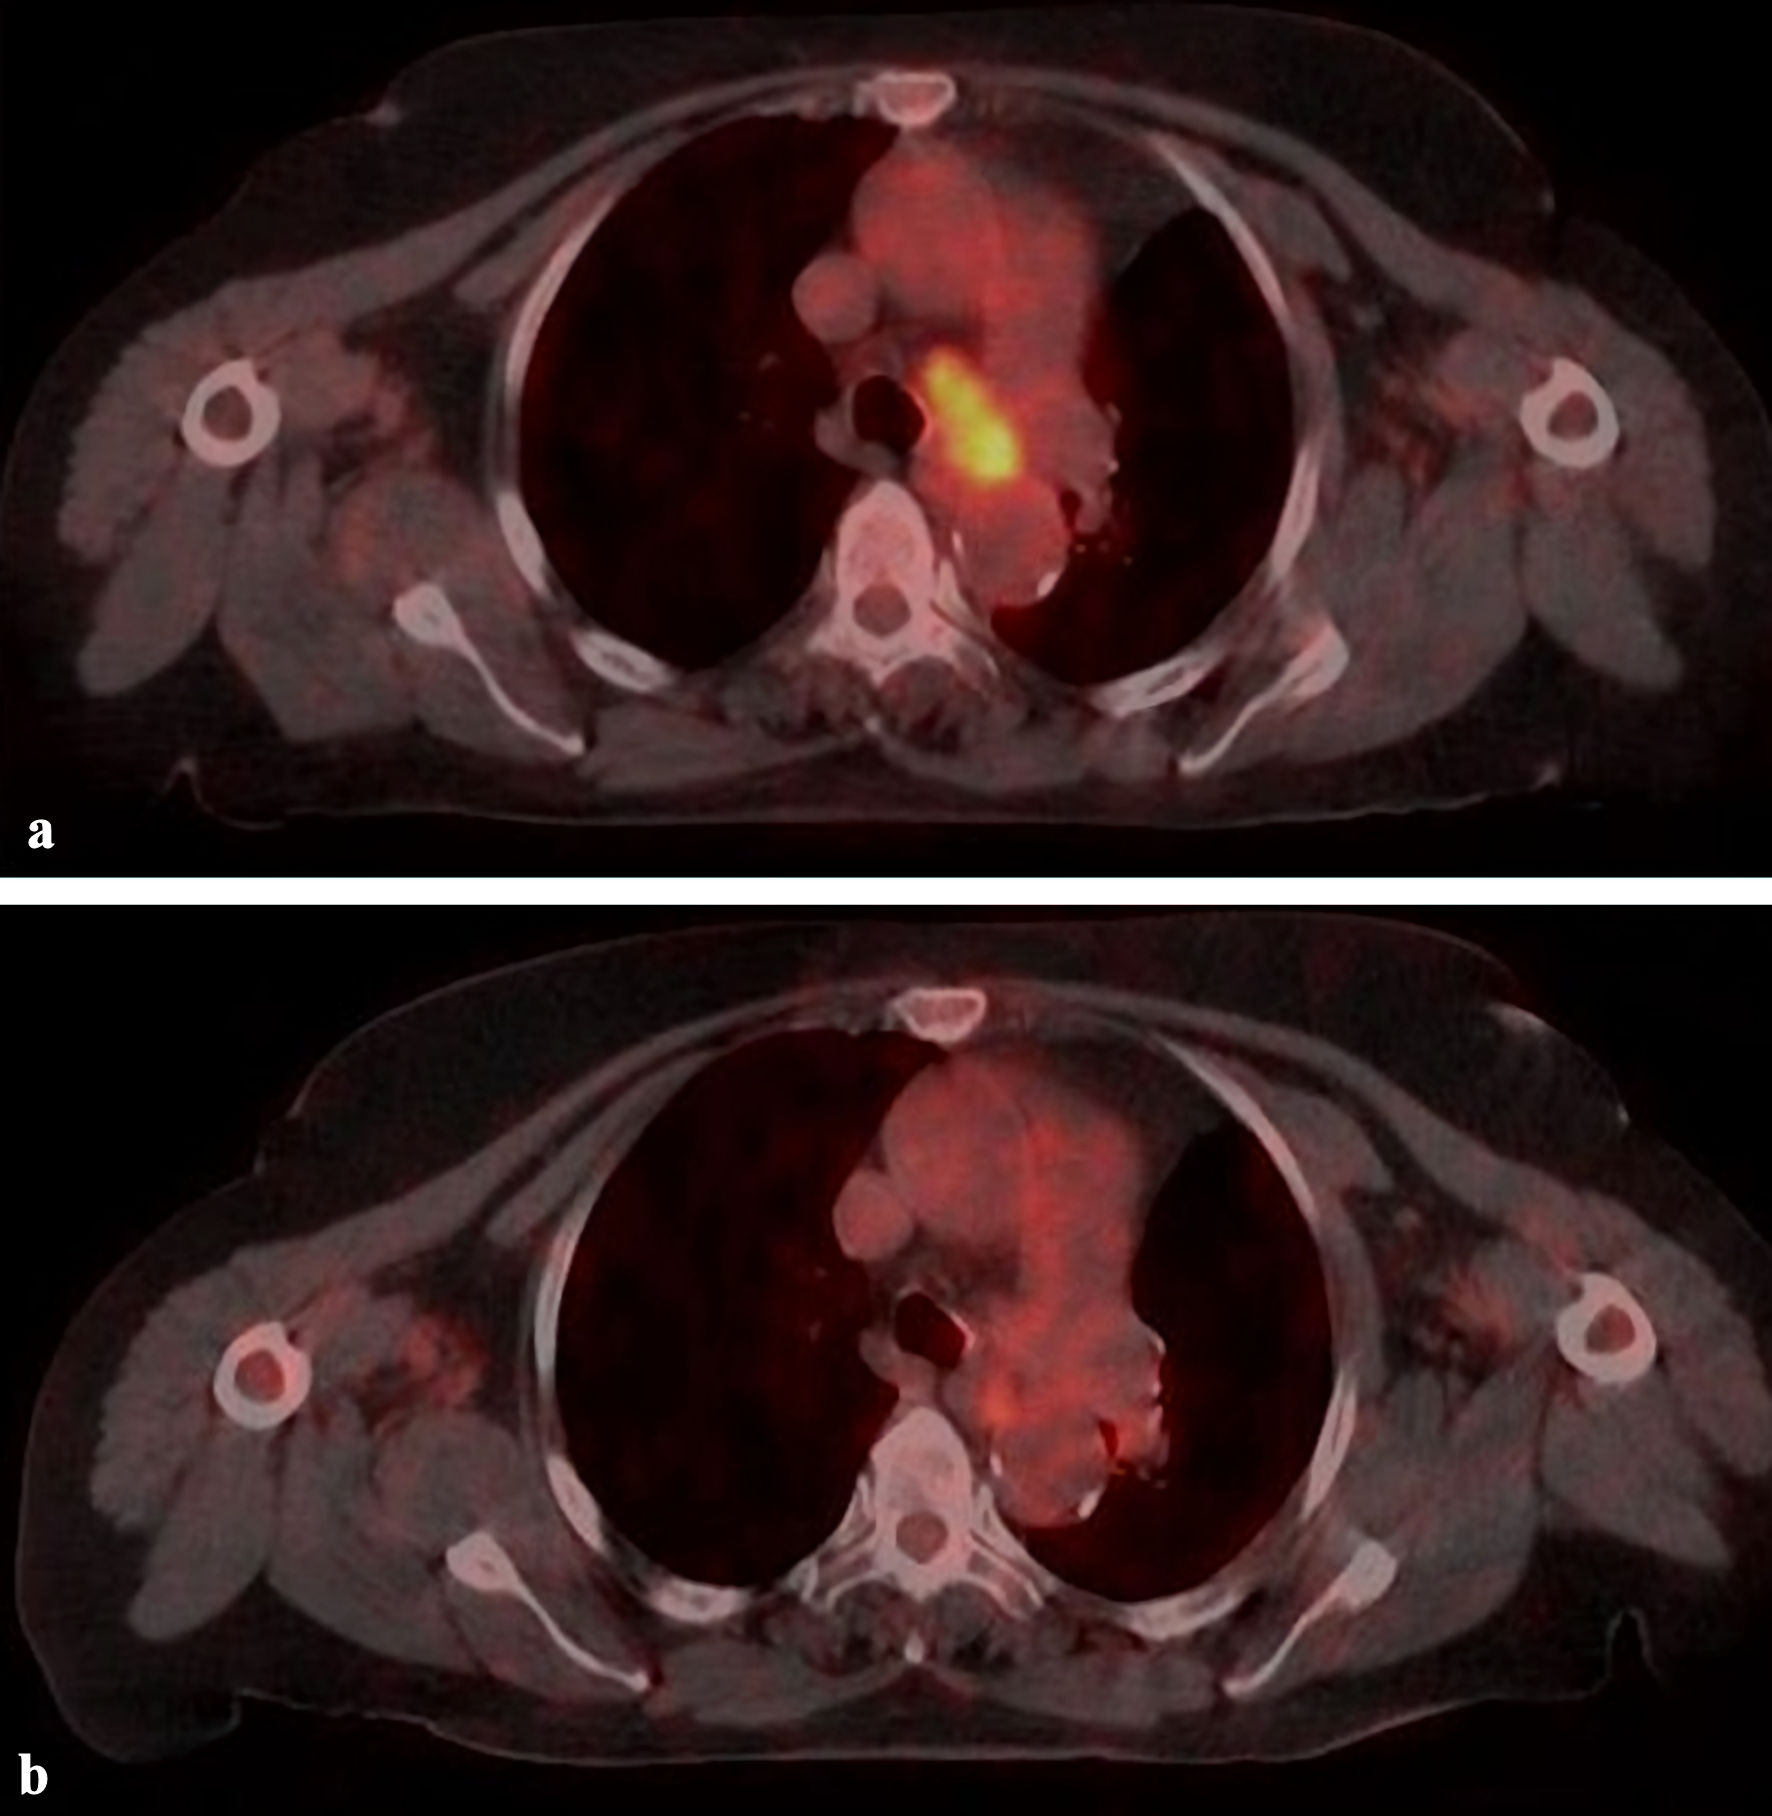

Patients were evaluated on February 1, 2023, with the median 20 months (2 - 46 months) follow-up time. Complete response (CR), partial response (PR), and stable responses were found in 26%, 62%, and 9.5%, respectively in 41 lesions at a median of 2 months (1- 6 months) (Table 1, Fig. 2). The median SUVmax value was 1.9 (0 - 4.8) for 37 lesions at the first evaluation after SBRT. At the 12th month evaluation, CR, PR, stable response, and local progression were found in 35.5%, 47.5%, 5%, and 12% of cases respectively for 42 lesions. CR was seen at median 6 months (3 - 12 months) in seven patients with PR or stable response at first evaluation. During the follow-up period, local recurrence developed in 10 lesions (24%) at median of 11 months (3 - 29 months). Local recurrence developed in 17% (4/23 cases), 33% (4/12 cases), and 28% (2/7 cases) in patients with primary lung, metastatic lung, and LN lesions, respectively. Fifteen patients died at a median of 15 months (2 - 22 months) due to existing cardiac morbidity (one case), COVID-19 pneumonia (two cases), lung infection (three cases), progression (four cases), and unknown reason (five cases). The mean, 1-, and 2-year OS were 31.5 months, 85.7%, and 54%, and the mean, 1-, and 2-year LRFS were 29.6 months, 76.7%, and 51%, respectively (Fig. 3).

![]() Click for large image | Figure 2. A case with lymph node (4L) metastasis treated with 39 Gy/6 fx. (a) PET/CT image before treatment. (b) Complete response with PET/CT at 4 months after treatment. PET/CT: positron emission tomography/computed tomography. |